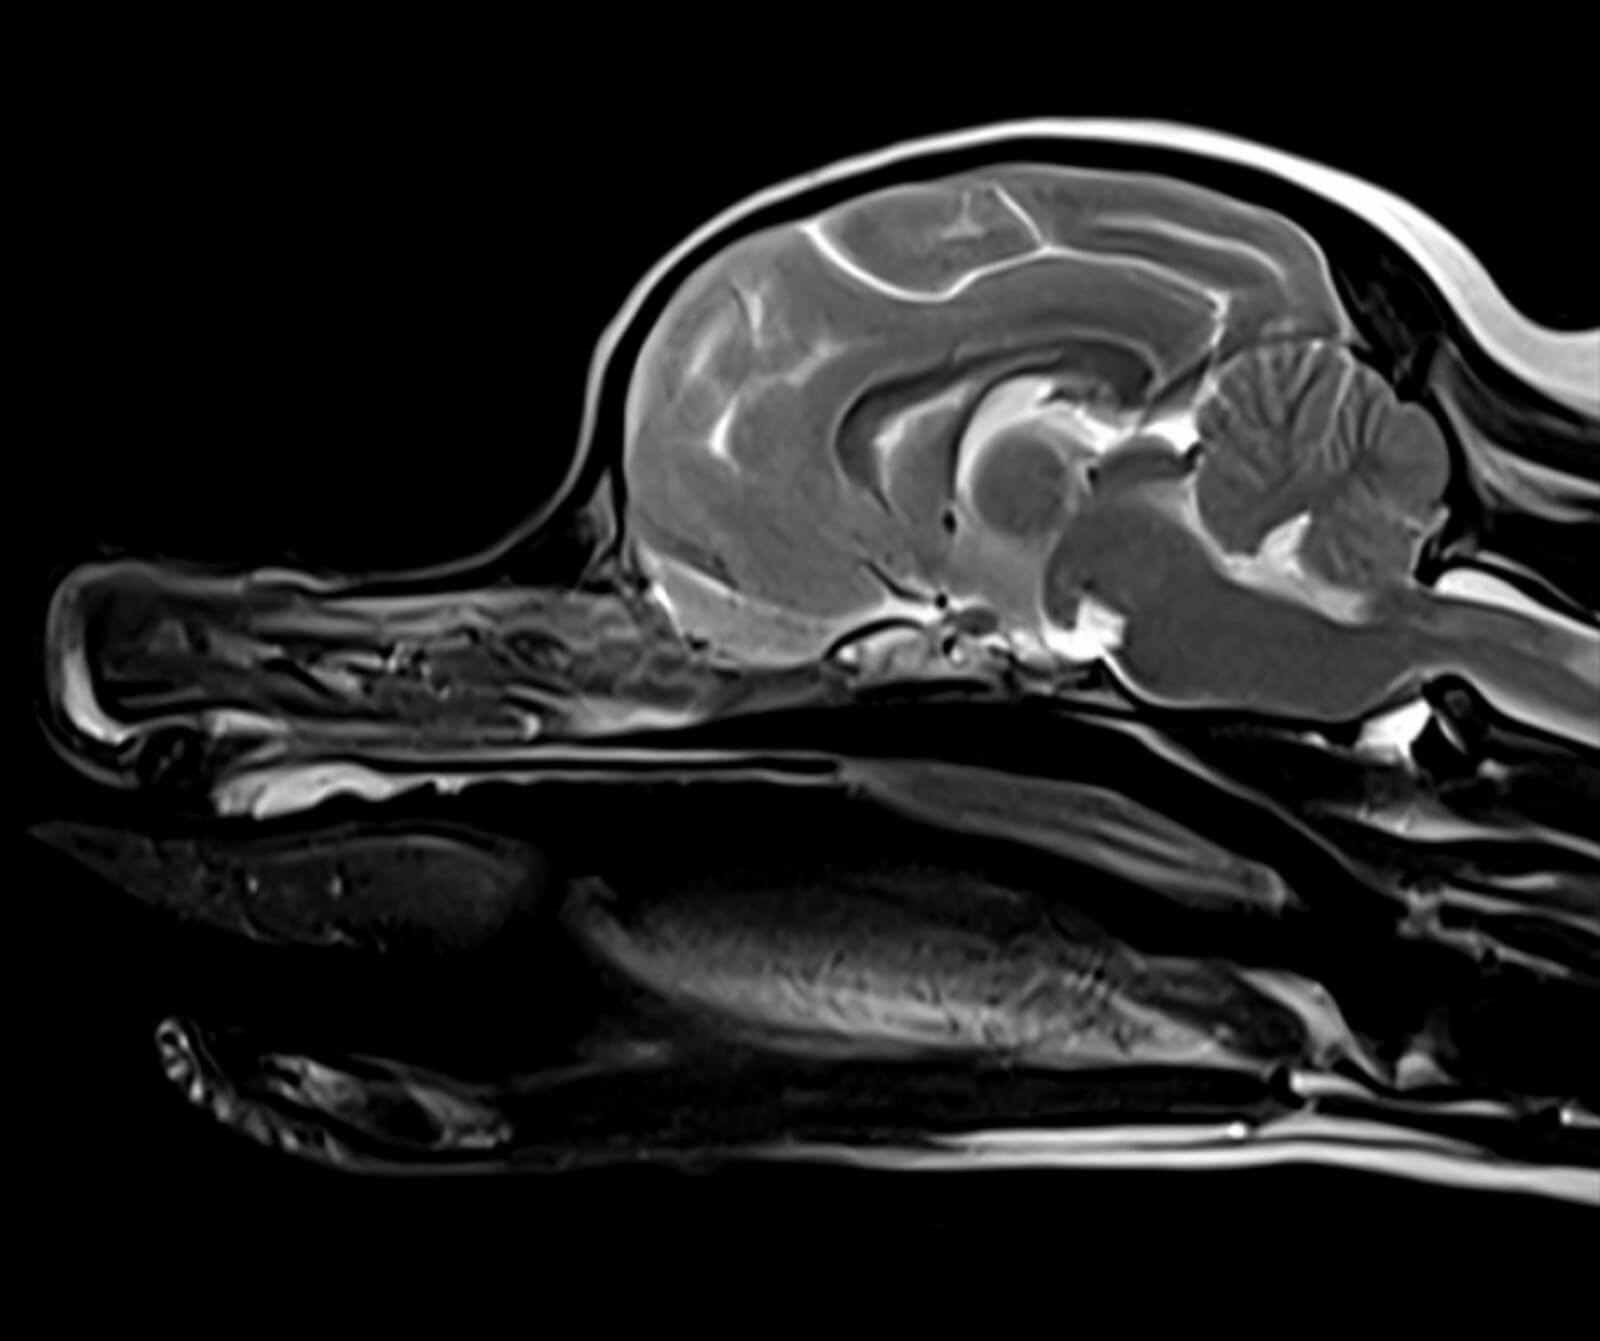

Manyetik Rezonans Görüntüleme (MR), sevimli dostlarımızın vücudundaki doku ve organların yüksek çözünürlükte, ayrıntılı ve güvenli biçimde değerlendirilmesini sağlayan ileri düzey bir tanısal görüntüleme yöntemidir. Radyasyon içermeyen bu yöntem, özellikle yumuşak dokuların detaylı incelenmesi gereken durumlarda en değerli tanı araçlarından biridir.

Veteriner hekimliğinde MR; beyin, omurilik, sinir sistemi, kas-iskelet sistemi ve iç organ hastalıklarının değerlendirilmesinde kritik rol oynar. Kemik yapılar dâhil olmak üzere vücudun tüm bölgeleri MR ile ayrıntılı şekilde incelenebilir.

• Beyin ve nörolojik hastalıkların değerlendirilmesi

Bu teknolojik altyapı sayesinde geniş görüntüleme alanlarında dahi yüksek çözünürlük ve detaylı kesitsel görüntüler sağlanırken, sevimli dostlarımızın anestezi altında geçirdiği süre optimum düzeyde tutulur ve tanısal doğruluk en üst seviyeye çıkarılır.

Veteriner hekimlik amaçlı kullanım için optimize edilmiş bu sistemler ile gerçekleştirilen görüntüleme incelemeleri Veteriner Manyetik Rezonans (Veteriner MR) olarak adlandırılmaktadır.